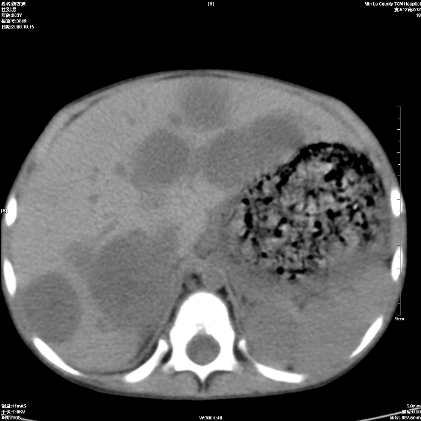

标题: PED1609:男性,3岁。彩超示肝Ca. [打印本页]

标题: PED1609:男性,3岁。彩超示肝Ca.

3岁;肝低密度灶;有钙化;有转移灶;考虑肝母细胞瘤;查afp

支持肝母细胞瘤肝内转移

考虑神经母细胞瘤并肝转移

考虑:1、右侧后下纵隔畸胎瘤。

2、肝脏多发血管内皮细胞瘤。

建议:增强确诊。